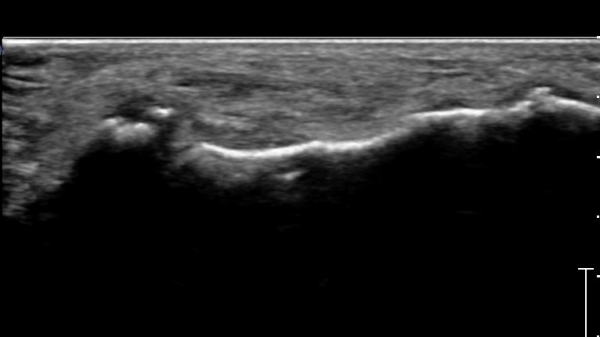

Á¾°ñÀÔ¹æ°ñ°üÀý Á¾´Ü¸é°Ë»ç»ó Á¾°ñ Àü¹æµ¹±â °ß¿­°ñÀý°ú Á¦4ÁßÁ·°ñ °ß¿­°ñÀýÀÌ °üÂûµÈ´Ù(»çÁø 2).